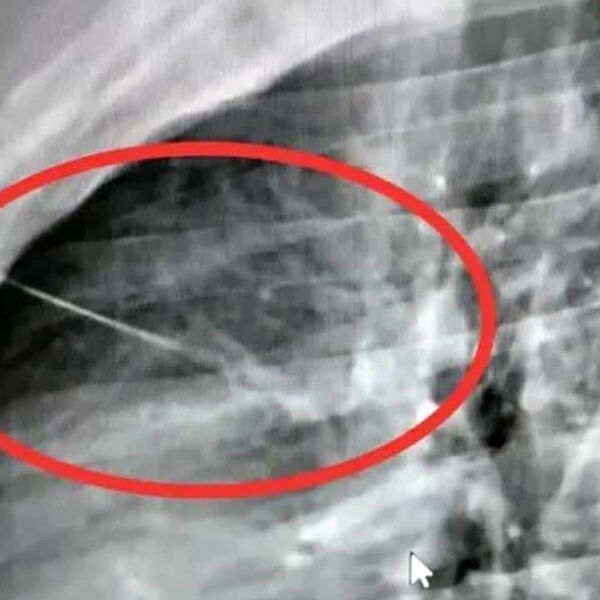

Рентген в местной больнице, куда сначала доставили тайца, показал острый посторонний предмет рядом с сердцем, позже медики установили, что это игла длиной около семи сантиметров. Пациента срочно перевели в крупную больницу Бурирама, чтобы провести высокорисковую операцию по удалению инородного тела.